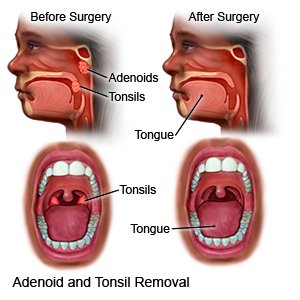

Overview

Package includes:

Days in hospital : 2 to 3 Days (For patient and one attendant)

Days in hotel : 7 Days (For patient and one attendant)

Room type in hospital : Shared

Room type in hotel : Private

Hotel category: Standard

Value added benefits of the Adenoidectomy:

Overview

Package includes:

Days in hospital : 2 to 3 Days (For patient and one attendant)

Days in hotel : 5 Days (For patient and one attendant)

Room type in hospital : Shared

Room type in hotel : Private

Hotel category: Standard

Value added benefits of the Tonsillectomy: